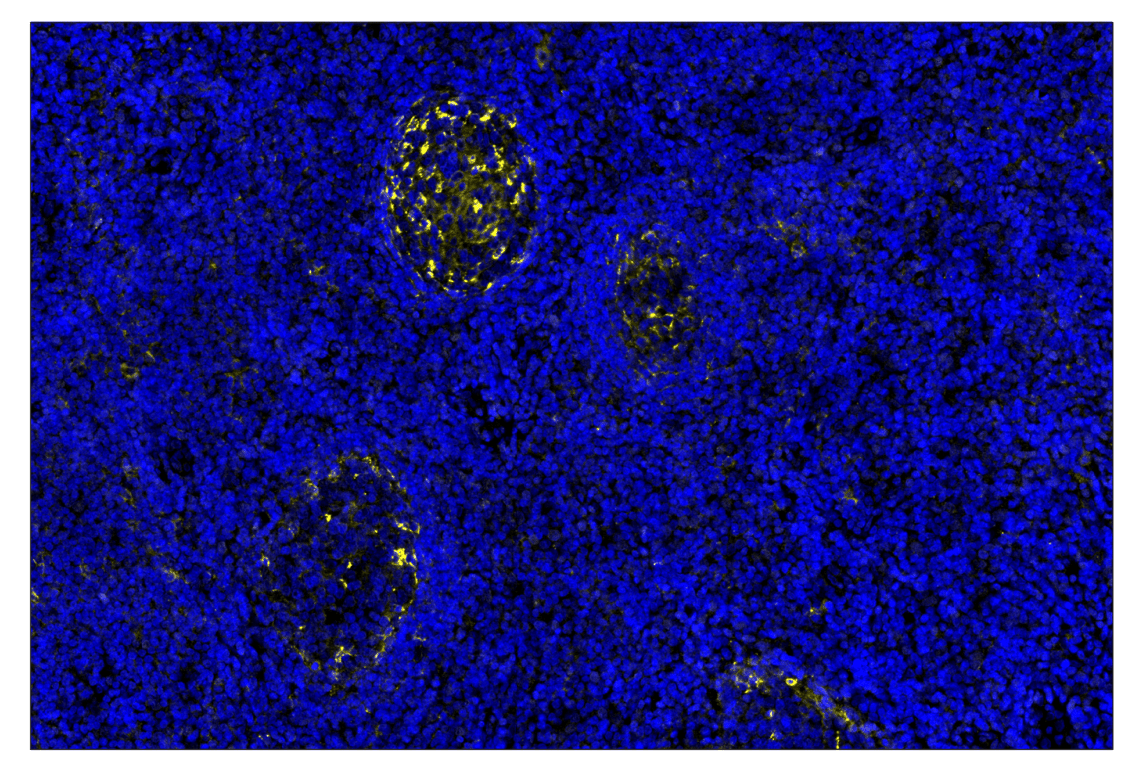

PD-L2 (D7U8C) & CO-0113-594 SignalStar™ Oligo-Antibody Pair #79988

| SignalStar™ Leica Bond | 1:50 - 1:200 |

SignalStar Oligo-Antibody Pairs are compatible with the SignalStar Multiplex IHC Buffer Kits for use in fluorescent multiplex imaging experiments. This product includes the oligo-conjugated antibodies and complementary oligos required for labeling your target protein on up to 10 slides. SignalStar Multiplex IHC Buffer Kits are required to amplify and image the target signal. Multiple oligo-antibody pairs can be conveniently combined into a multiplex panel using the SignalStar Multiplex IHC Panel Builder. SignalStar Multiplex IHC Kits & Reagents are not compatible with all of Cell Signaling Technology® products and protocols that are recommended for use in immunohistochemical assays.